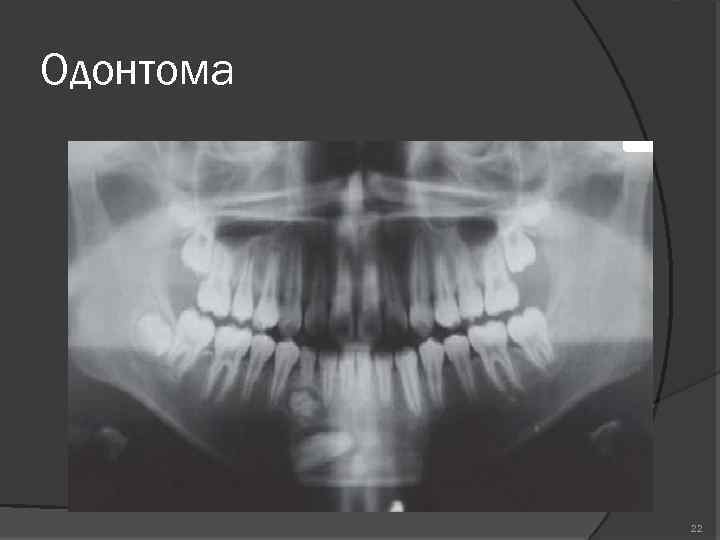

Одонтома нижней челюсти: фотографии и медицинская информация